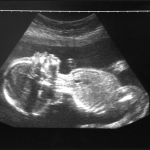

The scan said my baby wouldn’t live. It was wrong

When my unborn baby was a five-month-old fetus, twisting about in the internal dark, he was given a death sentence by a man I shall call Anton. We’d gone, my husband and I, for a 20-week scan at our local hospital. Anton was our designated sonographer; we arrived in his room bright-eyed and anxious, as